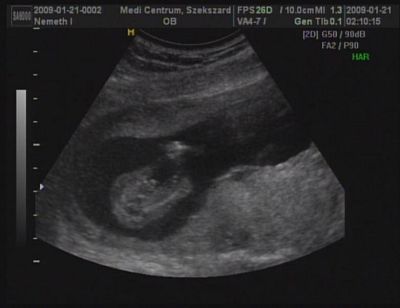

Amúgy uh közben mondta még a dokim, mintha csak úgy magának mormogná, hogy zárt mellkas, meg zárt gerinc, ilyeneket, úgyhogy azzal kapcsolatban már ott megnyugodtam.